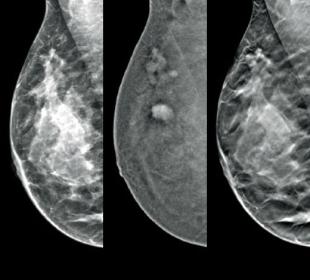

Screening og diagnose